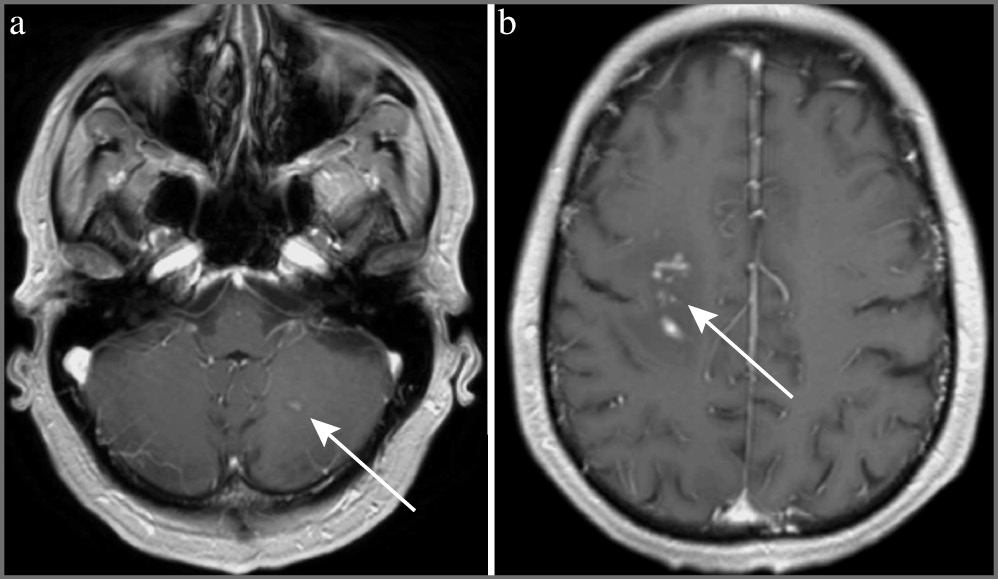

МРТ ГМ от 10.03.2021 с контрастным усилением: на полученных изображениях определяются очаги слева в полушарии мозжечка, справа в перивентрикулярной области и семиовальных центрах с признаками отека, слева у переднего рога. После введения контрастного вещества определяется патологическое накопление в очаге левой гемисферы мозжечка, справа в перивентрикулярной области (рис. 2).

Рис. 2. МРТ в Т1-взвешенном изображении пациента А от 10.03.2021. Патологическое накопление контрастного вещества в левой гемисфере мозжечка (а) и в перивентрикулярной области справа (b).